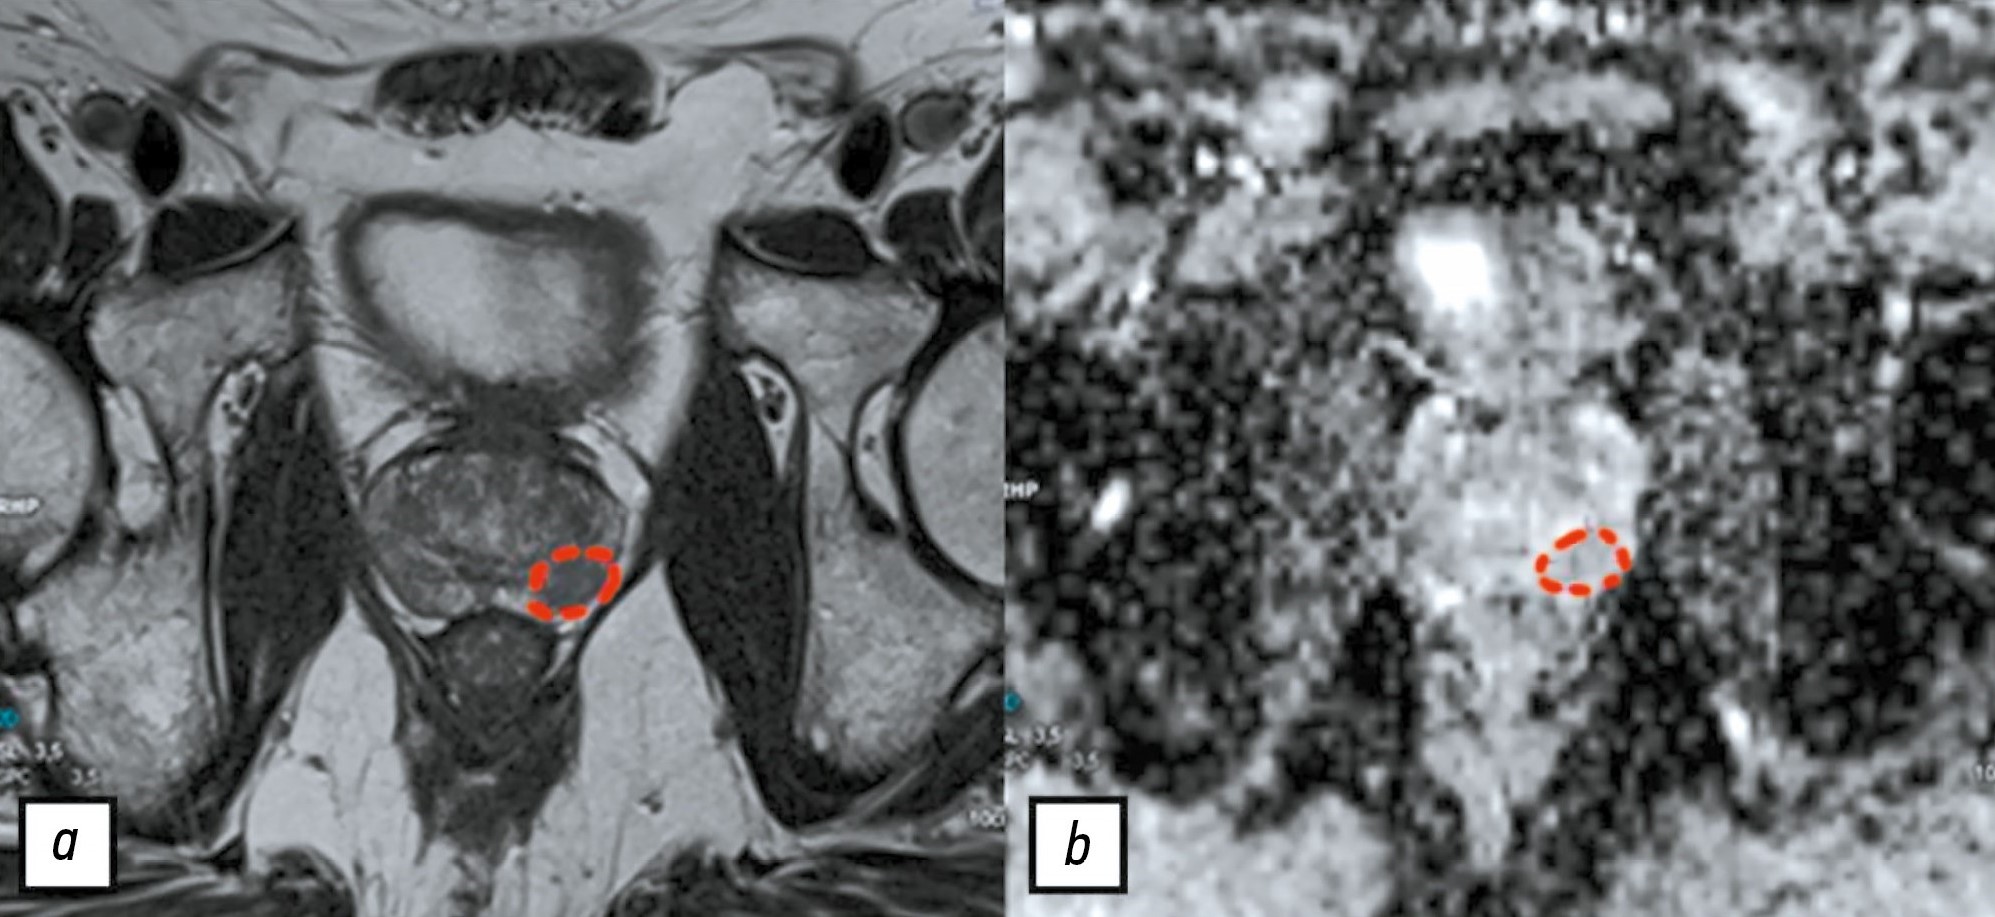

При создании набора данных1 один из экспертов подготовил референсные изображения, на которых схематически отметил интересующие патологические очаги на одном срезе, руководствуясь категорией PI-RADS и результатами мультифокальной фьюжн-биопсии (рис. 2). Таким образом, до начала настоящего исследования прошёл интервал более 6 месяцев после предыдущей работы эксперта с данными, что, согласно кривой забывания Эббингауза, является достаточным для минимизации влияния прежнего опыта на текущую разметку [17].

Рис. 2. Референсные изображения со схематически отмеченным очагом в периферической зоне левой доли простаты: a —Т2-взвешенное изображение; b — карта исчисляемого коэффициента диффузии.

В настоящем исследовании разметку проводили согласно этим изображениям на всех срезах, содержащих, по мнению разметчика, патологический очаг. Мы посчитали данный шаг оправданным как для удобства разметчиков, так и для уменьшения числа расхождений во время обработки результатов.